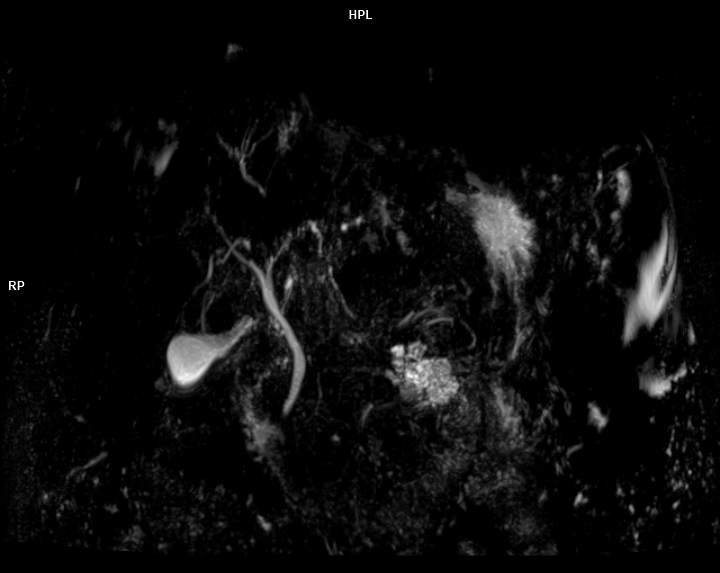

• 3 TESLA MR ÇEKİM GÖRÜNTÜLERİ

3 Tesla MR Çekim Görüntüleri

• 3 Tesla MR Çekim Görüntüleri